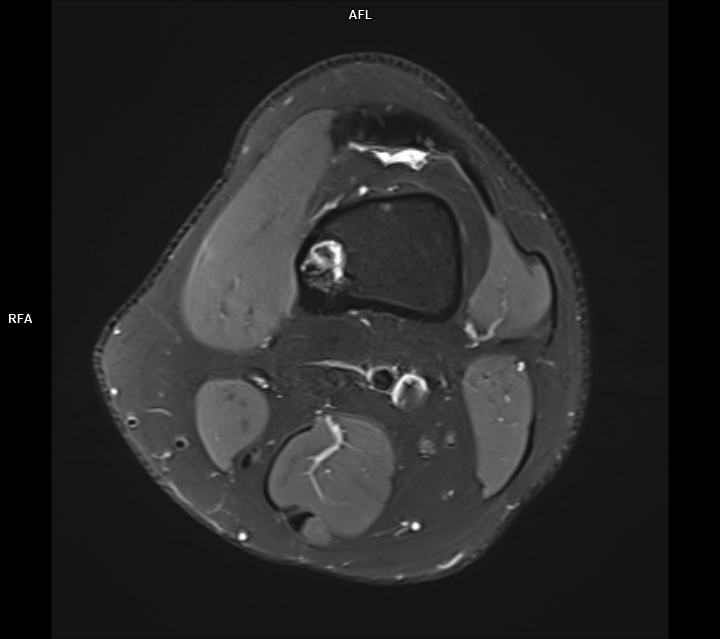

Figura 4: achiziție PD FS axial în plus față de achiziția T1 se evidențiază arii lichidiene în interiorul leziunii lipomatoase;